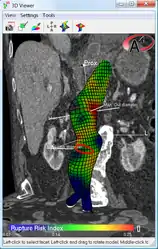

An aneurysm ruptures if the mechanical stress (tension per area) exceeds the local wall strength; consequently, peak wall stress (PWS)[29] and peak wall rupture risk (PWRR)[30] have been found to be more reliable parameters than diameter to assess AAA rupture risk. Medical software allows computing these rupture risk indices from standard clinical CT data and provides a patient-specific AAA rupture risk diagnosis.[31] This type of biomechanical approach has been shown to accurately predict the location of AAA rupture.[32]

Biomechanical AAA rupture risk prediction